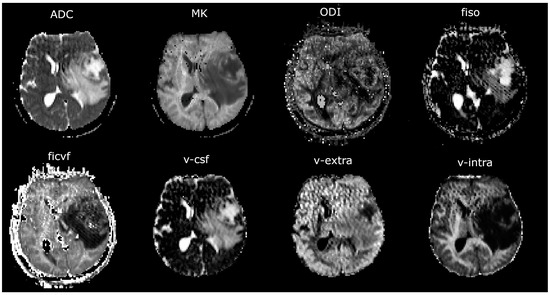

2.4. Image Analysis